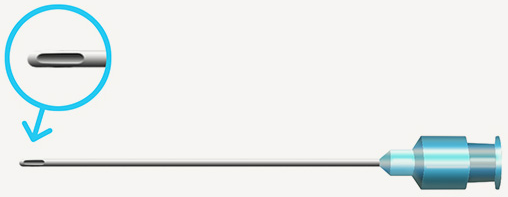

캐뉼라를 이용한 필러 시술로

조직·혈관 손상의 합병증 최소화!

바늘의 굵기가 가늘고 끝이 둥글어 피부조직과 혈관에 손상이 적고, 따라서 멍과 부기가 적은 게 장점이며

다양한 크기의 캐뉼라가 있어 개개인의 피부상태에 따라 알맞은 크기의 캐뉼라를 사용합니다.

둥근 캐뉼라

끝이 뭉뚝한 관모양으로 되어 있고, 구멍이 옆 부분에 위치해 있습니다.

캐뉼라는 멍이나 출혈 등의 자극을 유발하지 않으면서

시술 시 통증 또한 적다는 장점이 있습니다.